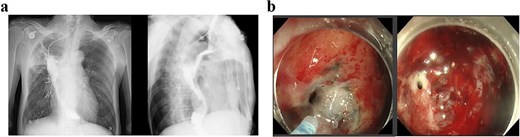

Following successful control of the pulmonary infection with conservative therapy, two bronchial stents were placed via fiberoptic bronchoscopy in the right mainstem bronchus to isolate the fistulous tract and prevent recurrent infection. Follow-up bronchoscopy after 2 weeks confirmed complete closure of the tract (Fig. 4), with resolution of infection markers and normalization of laboratory parameters. Fasting and gastric decompression were maintained to facilitate pleural tissue repair. After observing adequate thickening of the visceral pleura, oral intake was cautiously reintroduced, progressing from liquids to semisolid foods over 3 months. The patient tolerated this transition without infection recurrence, with sustained normalization of clinical and laboratory findings.

(a) Status following bronchoscopic stent placement. (b) Follow-up bronchoscopy demonstrating healed fistulous tract 2 weeks postintervention.